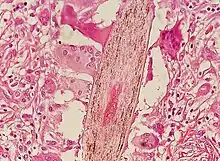

Folliculitis starts with the introduction of a skin pathogen to a hair follicle. Hair follicles can also be damaged by friction from clothing, an insect bite,[5] blockage of the follicle, shaving, or braids that are too tight and too close to the scalp. The damaged follicles are then infected by Staphylococcus. Folliculitis can affect people of all ages.